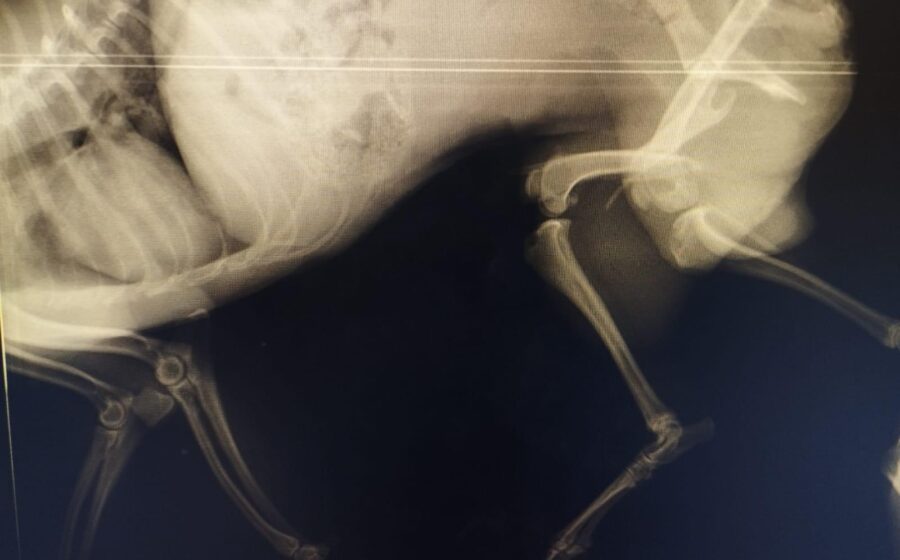

Er hat bereits eine Operation am Bein hinter sich. Doch ein neues Röntgenbild zeigt, dass leider auch seine andere Hüfte gebrochen ist. Eine zweite Operation ist daher notwendig. Danach benötigt er eine spezielle physiotherapeutische Betreuung, um wieder vollständig auf die Beine zu kommen. Er ist ein Kämpfer und hat es so sehr verdient, endlich schmerzfrei zu leben.